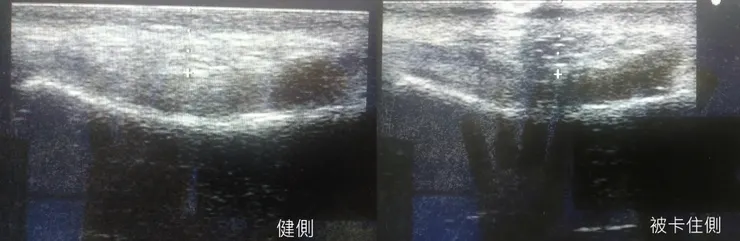

這次來是因為右手食指的板機指,也不是第一次發作。因為A1 pulley沒有明顯的腫大,所以開始找其他原因。

後來發現因為繭太大太硬了,影響了屈指肌肌腱的滑動。

老闆太認真,蔥油餅都是自己手工製作的,切蔥擀麵糰都自己來,所以手上長了繭,繭壓到了手指頭的屈指肌肌腱,影響了屈指肌肌腱的滑動,導致板機指。